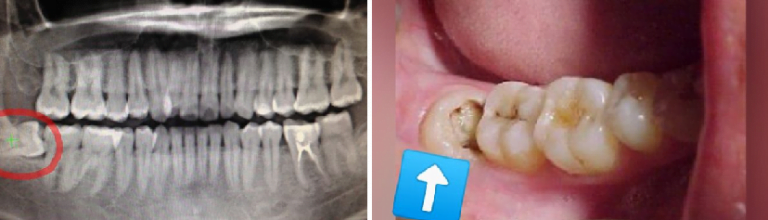

5 Petua Rawatan Pertumbuhan Gigi Bongsu Yang Memeritkan!